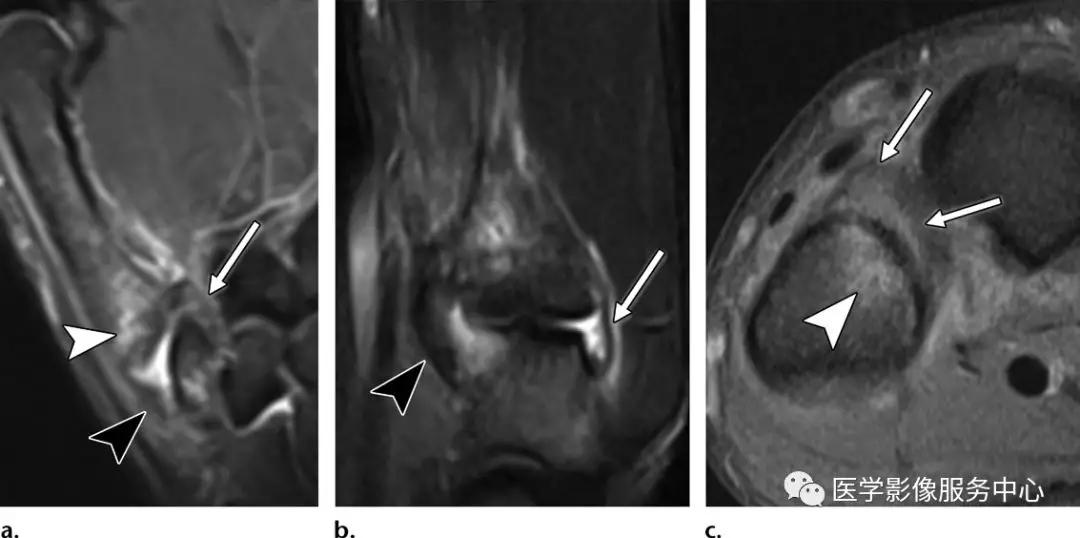

尺侧副韧带的撕脱损伤:

(左)第一指骨近端尺侧的尺侧副韧带撕脱骨折。

(中)白色箭头显示尺侧副韧带的全层紊乱,尺侧副韧带的正常解剖关系是位于内收肌腱膜(黑色箭头)的深部。

(右)Stener病变,伴尺侧副韧带损伤,撕脱的骨片被牵拉回缩(白色箭头)。

桡侧副韧带撕脱损伤:

(左)撕脱骨片略示移位(白色箭头),累及桡侧副韧带在第一近端指骨桡侧基底部的连接处。(右)桡侧副韧带从其指骨连接处的部分层厚撕裂(白色箭头),不伴有撕脱骨折。注意尺侧副韧带损伤也存在(白色长箭头)